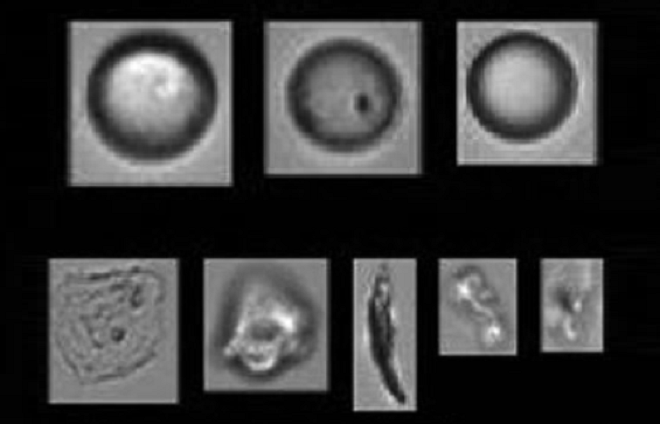

It is important to characterise the sub-visible particle population with methodologies such as flow-imaging microscopy. This enables differentiation of silicon oil droplets from proteinaceous particles, which is valuable as some protein formulations are sensitive to silicon oil, resulting in proteinaceous particles. Such studies are also helpful when changing from a vial to a delivery device, given that this results in higher sub-visible particle counts are expected, yet, typically, not of any clinical significance.